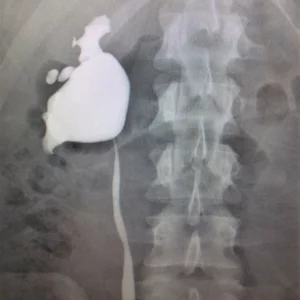

Renal arteriogram

A renal arteriogram is a special type of X-ray picture that helps doctors see the blood vessels in your kidneys.